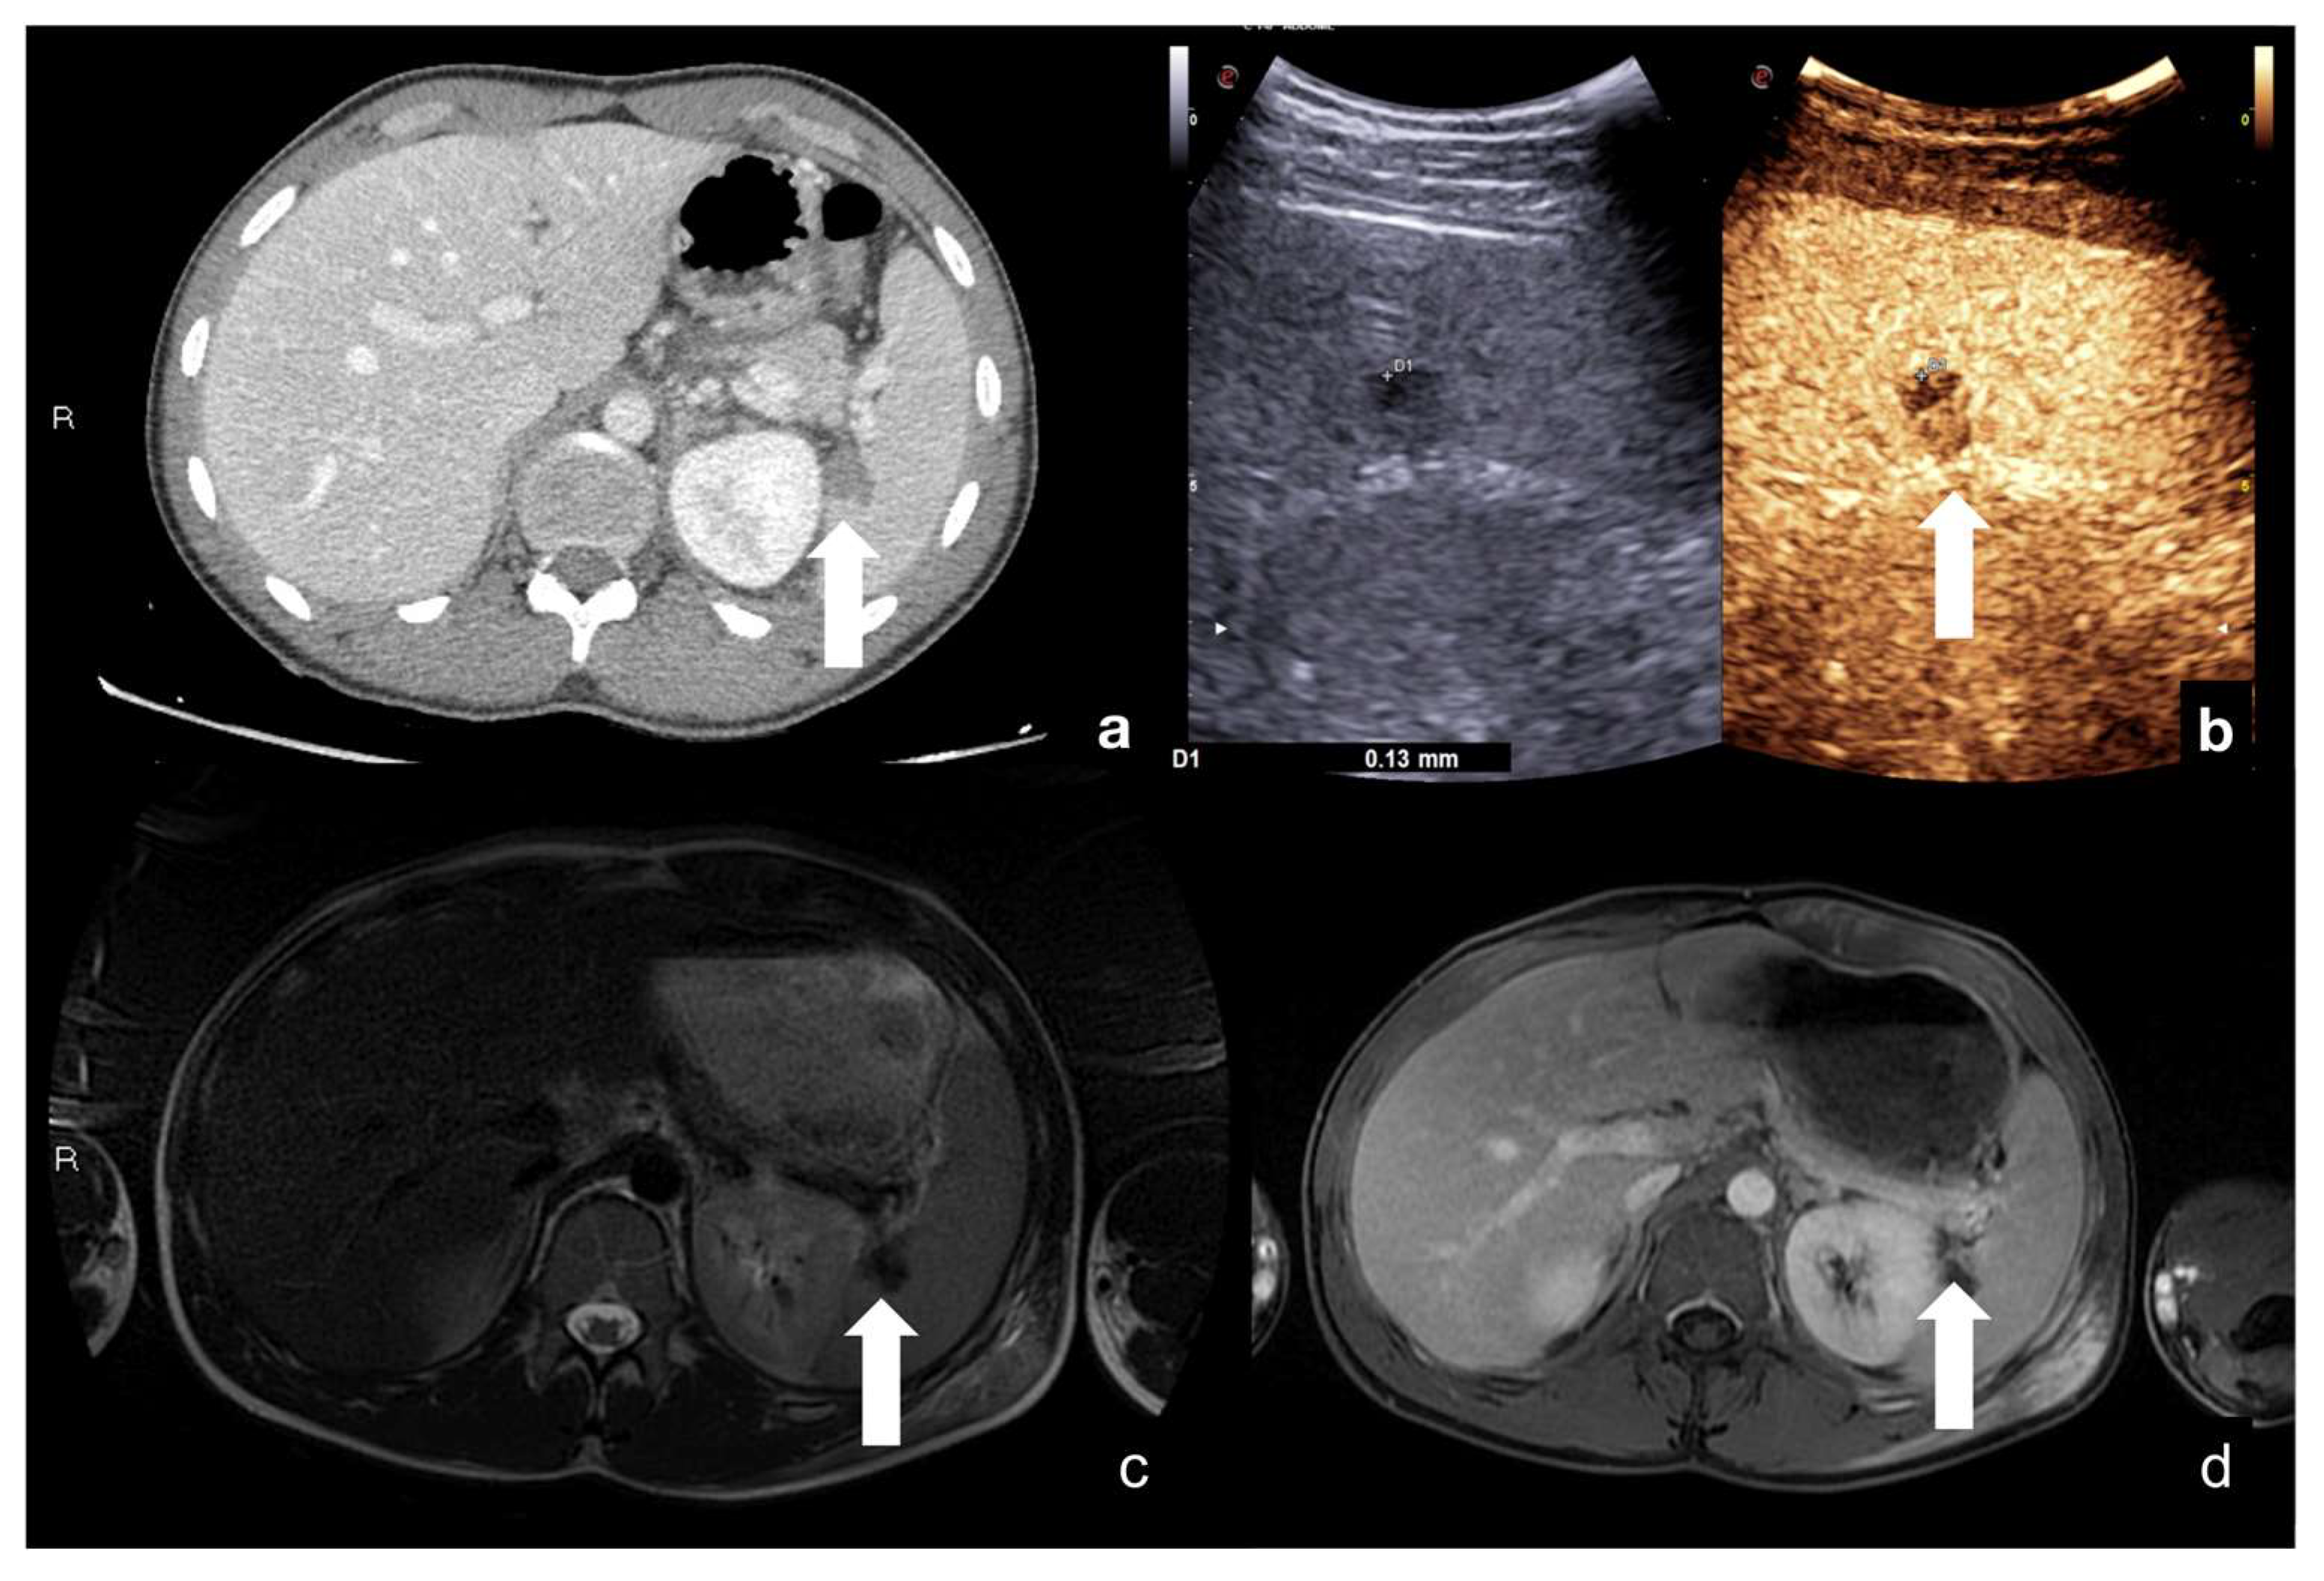

Intraparenchymal haematoma: the haematoma appears as a focal non-enhancing elliptic collection in the parenchyma with poorly defined irregular margins and no internal enhancing vessels. It does not involve interruption of the organ capsule and is particularly evident during the venous phase of the study (Figure 10 and Figure 11) [12,30].

Figure 10.

CT (a,d) and follow-up CEUS (b,c,e,f) of the right kidney in a 57−year-old patient who fell from a height. Follow-up CEUS was performed four days after the admission CT. Note at CEUS the progressive enhancement, at different time points, of the renal cortex in about 30 s (b,c) and the medulla, up to 2.5 min (e,f). The parenchymal hematomas appear as non-enhancing collections (b,e, orange lines) contained in the organ capsule (b, pink lines), without internal enhancing vessel or associated vascular injuries. Due to the physiological evolution of the hematoma, the follow-up, it shows small fluid anechoic areas related to the progressive resorption (e, arrow). Adopted from ref. [30], 2021, Iacobellis, F.; et al.

Figure 11.

Adrenal gland hematoma. CEUS (a) and contrast-enhanced CT (b) of a 44−year-old male patient after a motor vehicle accident, showing right adrenal gland hematoma with no vascular complication. CEUS (c) and contrast-enhanced CT (d) follow up of a 36-year-old male patient on day 3 after a car accident; a pseudo-aneurysm within the right adrenal gland hematoma is visible (white arrows).